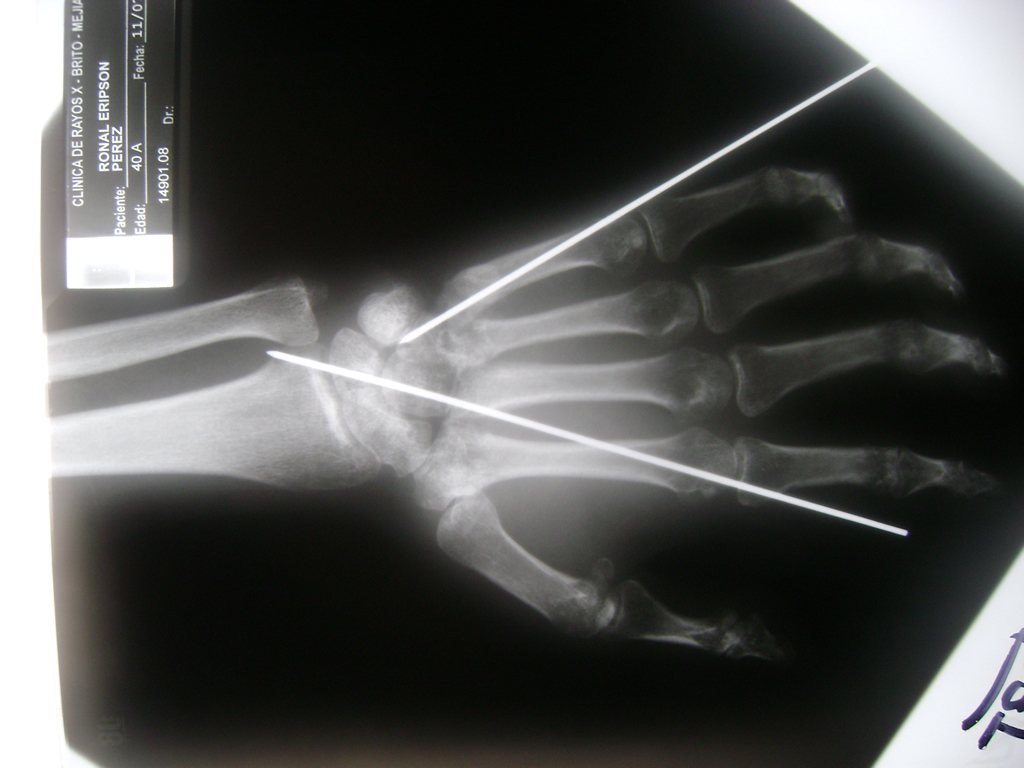

Cirugía de Fémur - Cirugías de Muñecas y Manos

Los procedimientos más comunes en cirugía de la mano son aquellos destinados a reparar traumatismos, incluyendo lesiones de tendones, nervios, vasos sanguíneos, y articulaciones; huesos fracturados; y quemaduras, cortes, y otros daños de la piel.